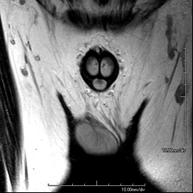

- Male pelvis MRI

This non-invasive diagnostic procedure uses an electromagnetic field and radio waves (from a transmitter and receiver) to acquire high-definition anatomical images of the male pelvis. It is a radiation-free procedure. No prior preparation is required. In some cases, paramagnetic contrast (gadolinium) is required to characterise the lesions. This test enables the assessment of organs such as the urinary bladder, the junction between the ureters and the bladder, the prostate, the seminal vesicles, the urethra, the pelvic bones, etc.